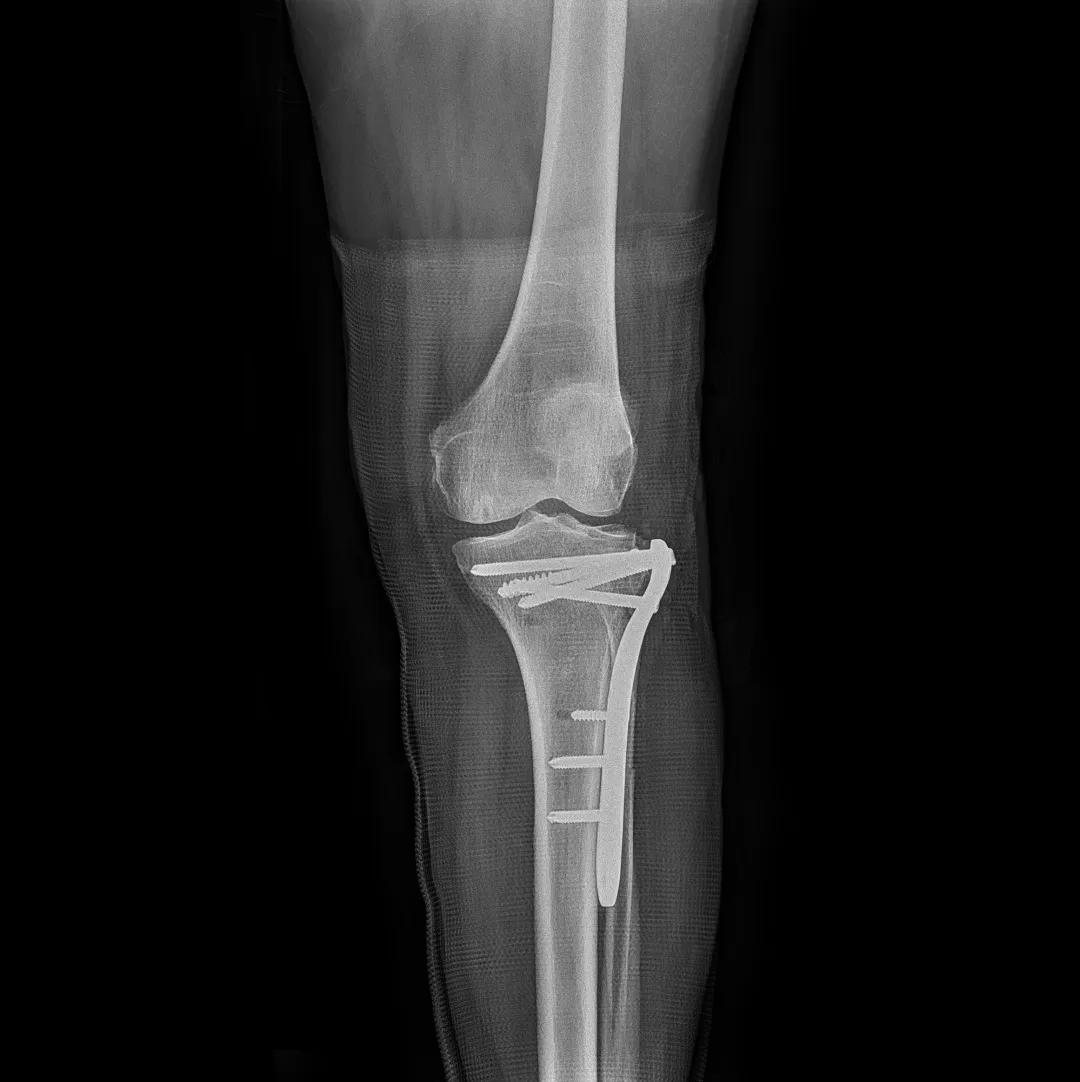

最后来看看“飞燕”的临床成像:

滑动查看更多图片